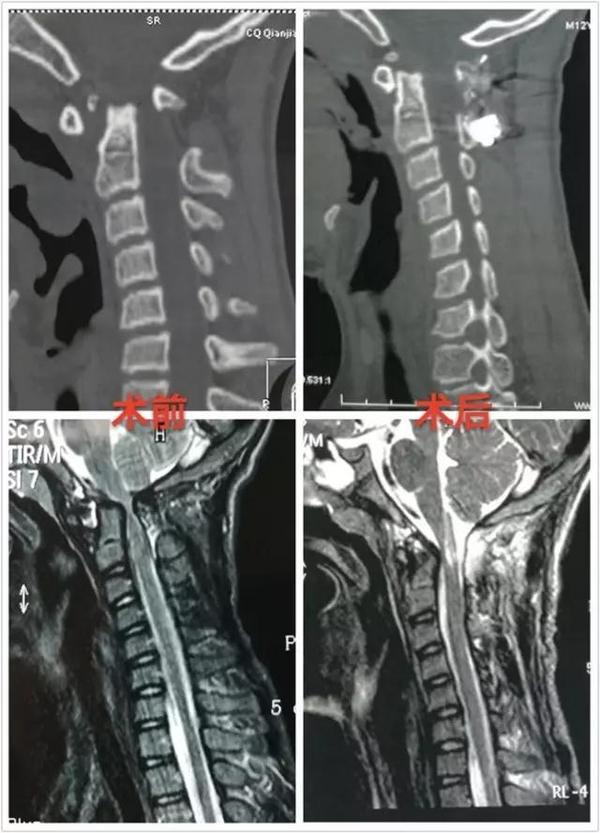

病例一:患者女性,49岁,因颈部活动受限4月入院,诊断为寰枢椎脱位,颅底

goel术式治疗寰枢椎脱位1例分享

寰枢椎脱位合并阻滞椎一例. 术者:孙晓立 助手:刘宏雷

寰枢椎脱位